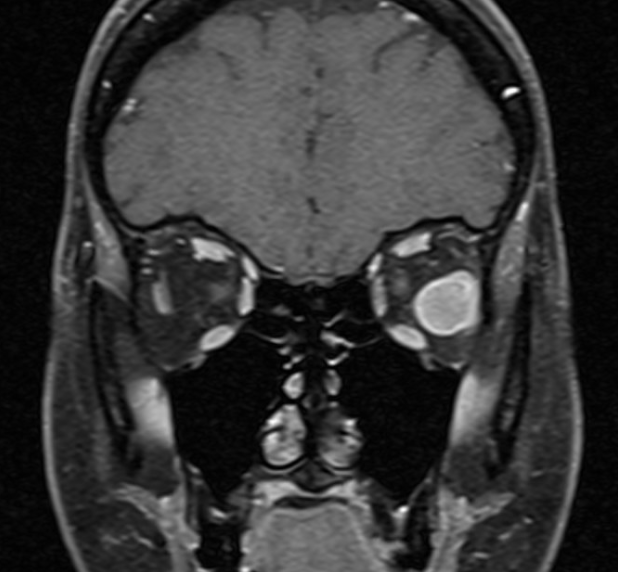

Coronal MRI of orbital GCT demonstrating avid peripheral enhancement